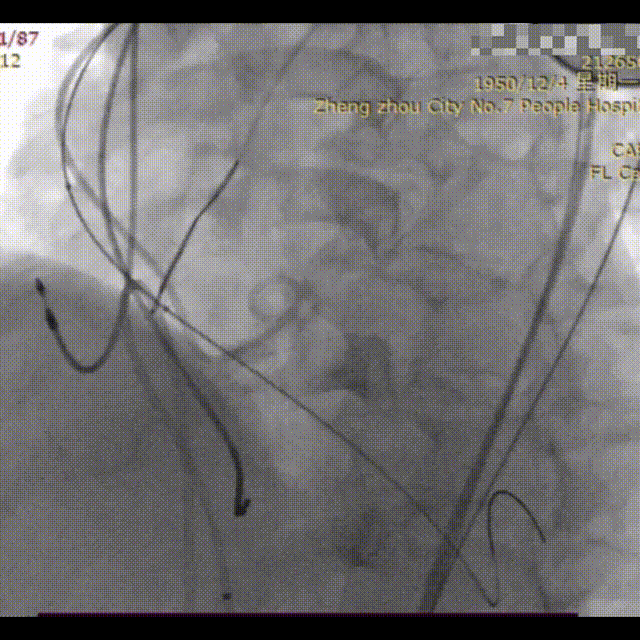

手术过程概览:

冠脉造影

瓣膜释放后形态位置良好,造影几乎无瓣周漏